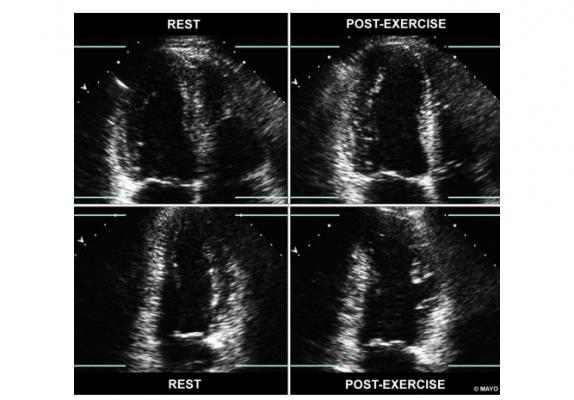

View What Will An Echocardiogram Show Pics. An echocardiogram checks how your heart's chambers and valves are pumping blood through your heart. An echocardiogram is a test that uses ultrasound to show how well your heart is working.

What does an echocardiogram show? An echocardiogram is used to show possible abnormalities of the heart structure and function that may be the cause for symptoms thought to be related to heart disease. An echocardiogram is a test that uses sound waves to create pictures of the heart.

An echocardiogram is a test done that observes the movements of the heart. Echocardiogram shows the size, structure, and movement of various parts of your heart. What it is, what it tests, types of echocardiograms, how to prepare, what happens during the test, and what the results show. An echocardiogram, or echo, is a scan used to look at the heart and nearby blood vessels.